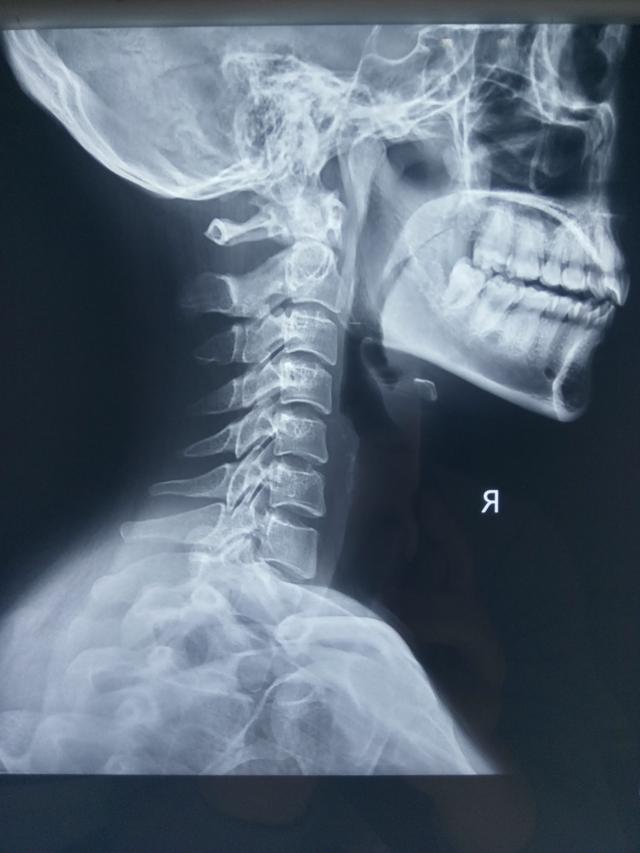

我的颈椎正常吗?

500x667 - 52KB - JPEG

不正常颈椎x光片图

500x332 - 21KB - JPEG